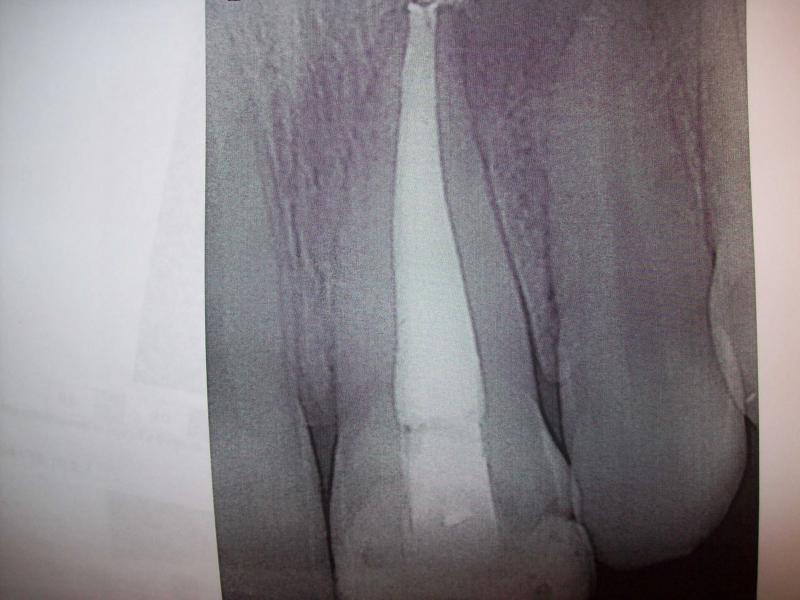

General Dentist,  Performs Root Canals ONLY - Microscope Trained Dentist

"DR. JET'S MISSION IS TO PERFORM  ROOT CANALS FOR A REDUCED FEE USING THE LATEST TECHNOLOGY  AND TECHNIQUES TO SERVICE THE MANY PEOPLE WHO ARE UNINSURED OR UNDER-INSURED GIVING EVERYONE AN OPPORTUNITY TO SAVE THEIR TOOTH!"